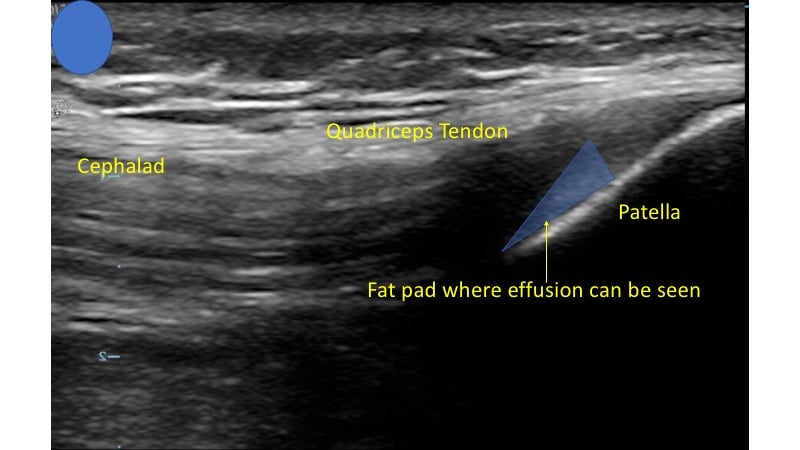

- In this view you should be able to identify the quadriceps tendon attached to the patella.

- Deep to the tendon and proximal to the patella you should be able to identify the suprapatellar fat pad superficial to the femur. (Fig. 4)

- Figure 4. Ultrasound demonstrating normal knee

- This will be displaced by joint effusion when a significant amount of fluid exists in this space.4 (Video 1)